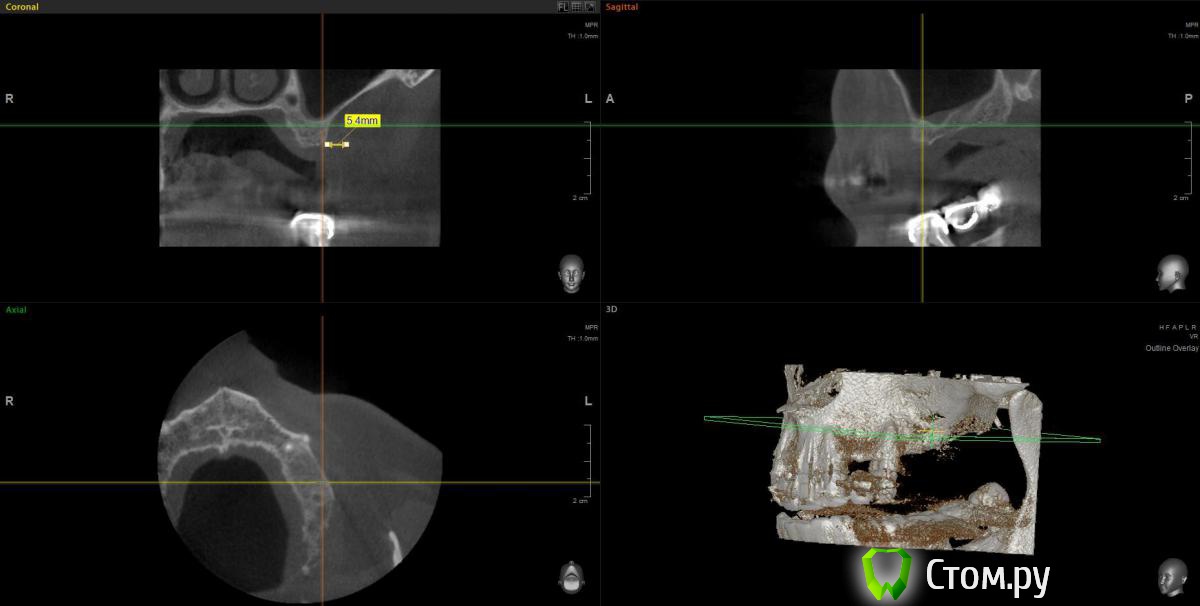

wladdX Опубликовано 11 февраля, 2014 Поделиться Опубликовано 11 февраля, 2014 (изменено) Прошу прощения за вторжение в чужую тему (администратор, поправьте), но ситуация похожа. Т.е. помимо синус-лифтинга надо увеличить ширину альвеолярного отростка. Предполагаю поступить примерно, как продемонстрировал Mane выше. Но может подойдёт "метод полужёстких каркасов? Кстати септа в пазухе замысловатая. По поводу остальных сегментов и прочих проблем - пациент на них не настроен, интересует его только зона 25,26,27 Изменено 11 февраля, 2014 пользователем wladdX Ссылка на комментарий